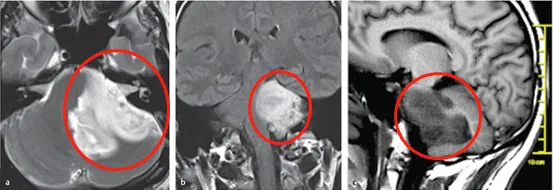

不能在这样下去了,H先生去到医院检查发现磁共振成像MRI显示“脑干部位巨大肿瘤”,累及左侧桥脑、脑桥臂和小脑,这个肿瘤压迫到了邻近的面神经、听神经,从而导致了他诸多症状的发生。

图a、b、c显示H先生脑干巨大占位,累及左侧桥脑、脑桥臂和小脑

图d:术前扩散张量成像显示脑干肿瘤占位,压迫皮质嵴髓束移位